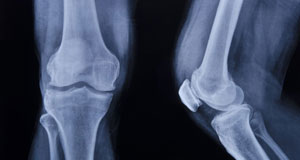

Rendgen dijagnostika kao pomoćno dijagnostičko sredstvo omogućava precizniju dijagnozu korišćenjem nativne i kontrastne tehnike.

Nativna tehnika pruža uvid u stanje koštanog sistema, mekih tkiva i pozicije eventualnih stranih tela.

Rendgen dijagnostika se najčešće koristi kod: akutnog abdomena, hroničnih oboljenja, povreda grudnog koša, zapaljenja pluća, povreda i zapaljenskih stanja zglobova, kičme, kod različitih tipova fraktura i slično.